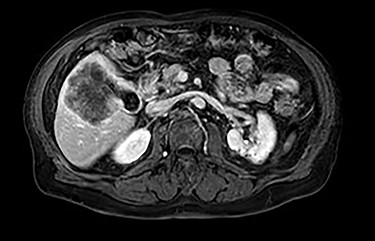

MRI demonstrated a 7.1 × 8.1 cm mass originating from the gallbladder that involved segments IVb, V, VI with areas of peripheral enhancement and central necrosis. Associated cholelithiasis was also noted. Figures 3–5 demonstrate the pertinent MRI findings.

MRI (axial view): 7.1 × 8.1 cm mass originating from the gallbladder involving segments IVb, V, VI with areas of peripheral enhancement and central necrosis.